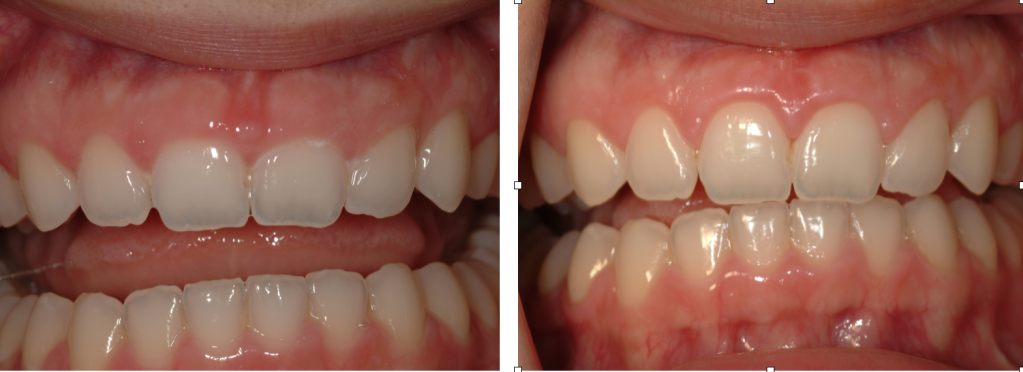

Esthetic crown lengthening